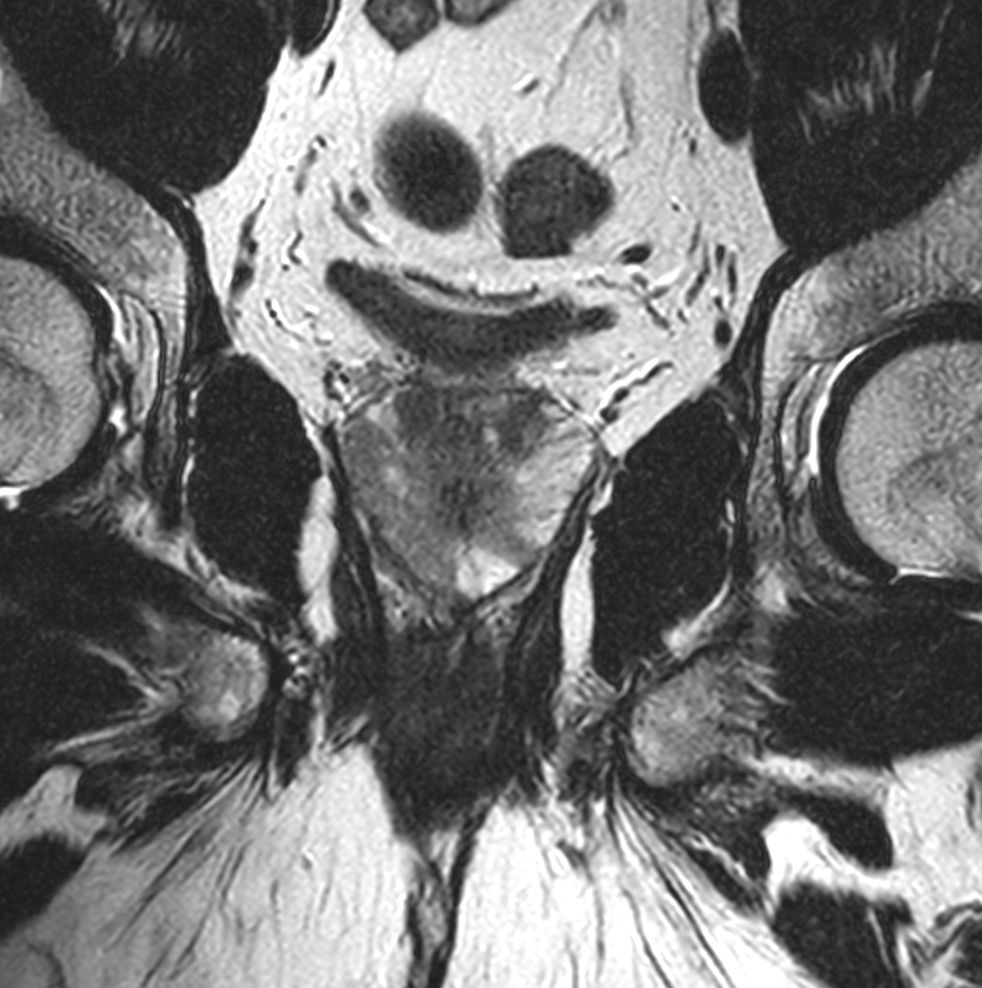

Coronal T2w TSE

Sagittal T2w TSE

Sagittal T2w TSE MultiVane XD